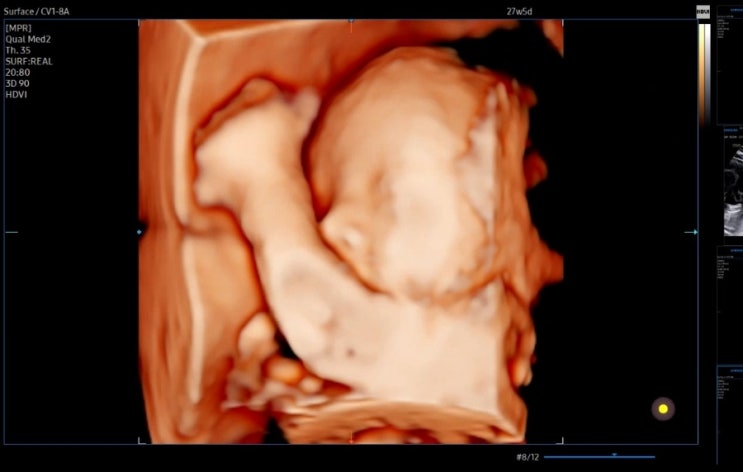

임신기록 ㅣ28w 입체초음파

배가 부쩍 많이 나오는 요즘이다......! 컨디션은 좋은데 불러오는 배때문에 허리가 슬 아프고 잘 때 바디...